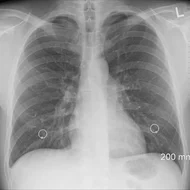

Március 23-án van A tuberkulózis (tbc) elleni küzdelem világnapja. A tuberkulózis más - néven gümőkor, tüdőbaj – egy baktérium által okozott megbetegedés, mely Magyarországon a védőoltásnak köszönhetően már csak ritkán fordul elő. A betegség megelőzhető és gyógyítható, azonban elhanyagolása halálhoz is vezet.

Március 23-án van A tuberkulózis (tbc) elleni küzdelem világnapja. A tuberkulózis más - néven gümőkor, tüdőbaj – egy baktérium által okozott megbetegedés, mely Magyarországon a védőoltásnak köszönhetően már csak ritkán fordul elő. A betegség megelőzhető és gyógyítható, azonban elhanyagolása halálhoz is vezet.

Március 23-án van A tuberkulózis (tbc) elleni küzdelem világnapja. A tuberkulózis más - néven gümőkor, tüdőbaj – egy baktérium által okozott megbetegedés, mely Magyarországon a védőoltásnak köszönhetően már csak ritkán fordul elő. A betegség megelőzhető és gyógyítható, azonban elhanyagolása halálhoz is vezet.